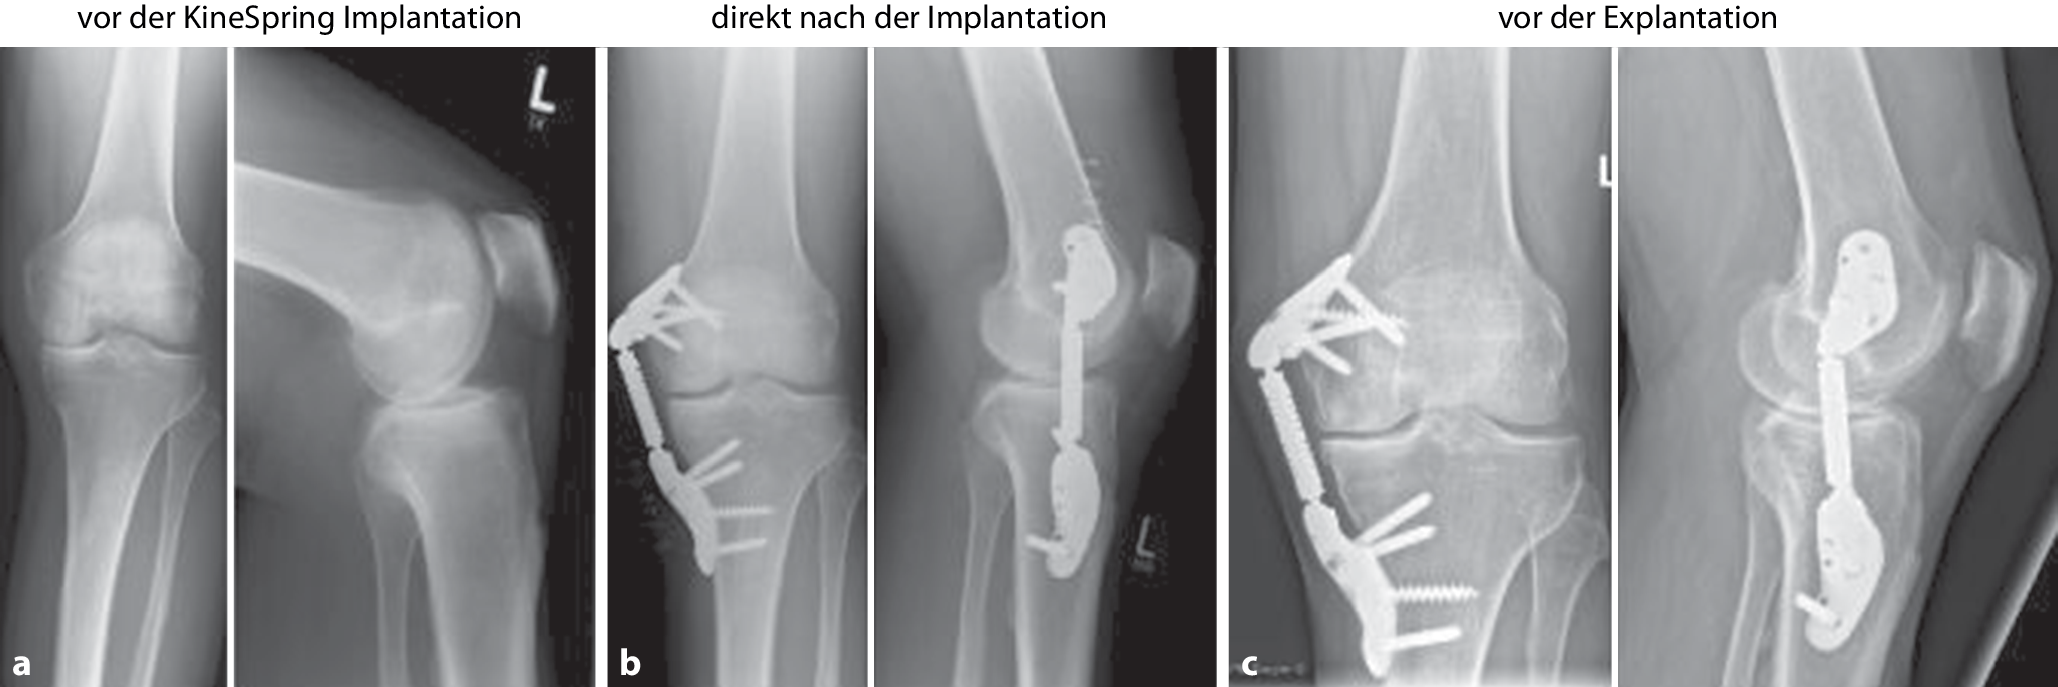

In der vorliegenden Bildgebung (Röntgenaufnahme Kniegelenk in 2 Ebenen) zeigte sich die regelrechte Implantatlage ohne Lockerungszeichen bei medialer Gonarthrose Grad 3 gemäß Kellgren-Lawrence (Abb. 2c). Aufgrund der zunehmenden Arthrose-assoziierten Beschwerden und radiologischen Arthrosemarker empfahlen wir eine offene Implantatentfernung und im Rahmen dessen eine diagnostische Kniearthroskopie und zweizeitig dann die Implantation einer Knieprothese. Es wurde ein zweizeitiges Vorgehen gewählt, da eine Studie zeigte, dass 22 (11 %) von insgesamt 203 Implantaten um Hüft- und Kniegelenke eine positive Sonikationskultur und eine signifikante bakterielle Besiedlung aufwiesen, obwohl keine offensichtlichen klinischen Symptome einer Entzündung vorlagen. Die häufigsten nachgewiesenen Bakterien waren Koagulase-negative Staphylokokken [11]. Des Weiteren hätte ein einzeitiges Vorgehen bedeutet, dass der Patient 3 Zugänge am Knie gehabt hätte: ein anteriorer für die Implantation der Knieendoprothese und zwei mediale, einer femoral und einer tibial, für die Explantation des KineSpring-Implantats, was das Weichteiltrauma bei einer Operation deutlich erhöht hätte.

Abb. 2

a Präoperative Aufnahmen in 2 Ebenen mit medialer Gonarthrose und deutlicher Verschmälerung des Gelenkspalts. b Postoperative Röntgenaufnahmen in 2 Ebenen nach Implantation des KineSpring-Systems (2012). c Präoperative Röntgenaufnahmen des Kniegelenks im Oktober 2024 vor der Implantatentfernung